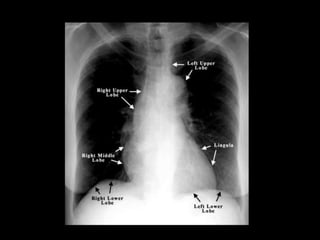

The document discusses the anatomy of the chest x-ray and CT scan by describing the lobes of the lungs and their locations. It also mentions the heart, mediastinum, hilum, and ribs. Several axial, coronal, and sagittal CT images are included with labels pointing out structures like the trachea, bronchi, lobes of the lungs, and fissures. In summary, the document provides an overview of lung and chest anatomy as seen on x-rays and CT scans through text descriptions and labeled medical images.